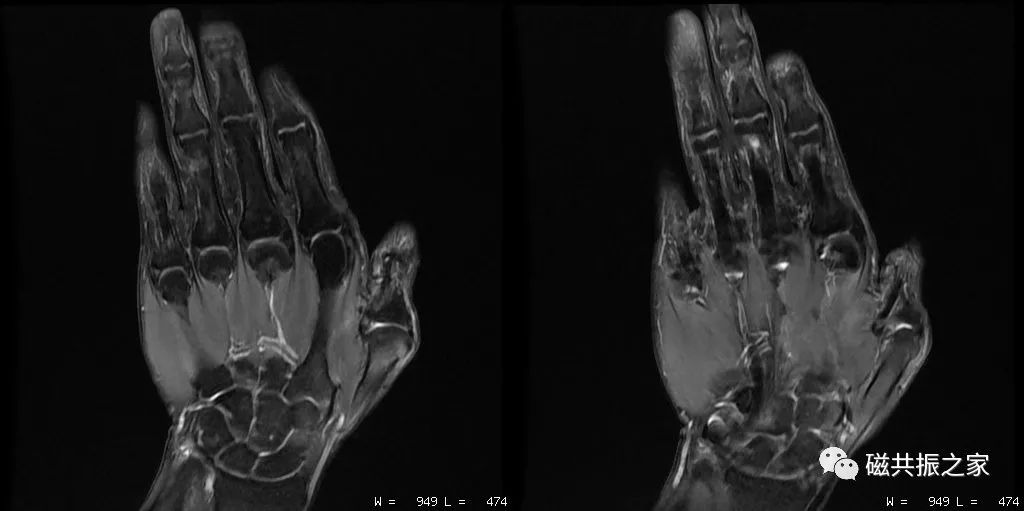

在进行四肢关节的扫描摆位时,首先要让被检者处于最为舒适的状态才能顺利地完成整个检查,特别是对于一些比较特殊的被检者。如上图△,对于该呈90°的肘关节的扫描,我们需要考虑选择何种线圈,被检者处于何种体位才能获得比较理想的图像质量。

除此之外,摆位时还需选择合理的线圈,抓住你需要观察的重点等,在其规范化摆位的基础上做到个性化的摆位。如上图△,对于足踝部的扫描,做好其压脂的均匀性是其难点之一,那么我们在进行该部位扫描时怎样摆位才能获得比较优异的图像。